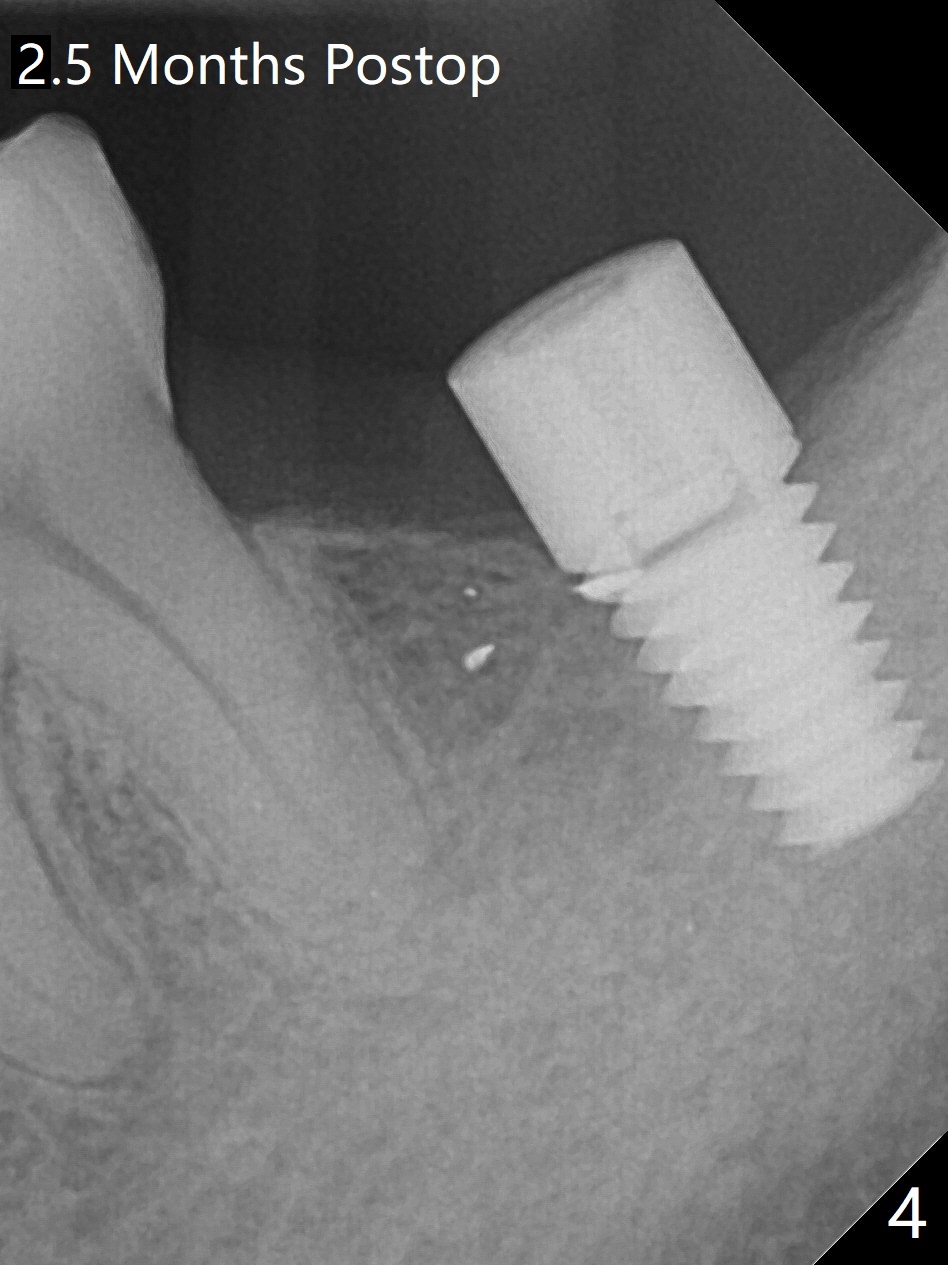

After finishing osteotomy with IS guide and Tatum Tapered tap 5x14 mm for 11 mm (gingival level) free hand, a 5x11 mm Tatum implant is placed at #18 with >15 Ncm (Fig.1). Bone harvested from the site of #18 will be used for #15 sinus lift (Fig.2 * as well as allograft). By the similar fashion, osteotomy at #15 is finished according to IS drill sequence except underdrilling (4.0x7.3 mm drill with 2 O-rings). Following use of DIO Sinus Approach Kit and placement of 2 pieces of PRF membrane and mixture of autogenous and allograft for sinus lift, a 4.5x11 mm IBS dummy implant is placed (Fig.2). With more allograft for sinus lift, a 5x9 mm implant is inserted with >35 Ncm (Fig.3). At #18 the implant 2.5 months postop (Fig.4) seems ok with removal of the cover screw and placement of a healing cuff. The implant at #15 appears osteointegrated with sinus lift 2.5 months postop (Fig.5 *). Half month later, the implant at #18 is tender associated with unipost placement. The healing abutment returns. A pair abutment (5.5x4(4) mm; 25 Ncm) is placed at #15. When the patient returns 7 months postop, BWs are taken to confirm that the abutment at #15 is fully seated, whereas that at #14 is not (Fig.6). A healing abutment is then placed at #14. Osteointegration seems to occur at #18; there is no tenderness when a 4.5x3 mm abutment is placed (Fig.7). Provisional crowns are fabricated at #15 and 18 for progressive loading. When the patient returns 14 months postop, a 5x4(4) mm hex abutment is placed at #14 with apparent gap between the implant and abutment (Fig.8 (PA) open arrow). In fact the gap seems to be absent more coronally as shown by bitewings (Fig.9,10 <). All of the 3 crowns are cemented in situ (Fig.11, 12) although the one at #14 is removed with the abutment for removal of residual cement. When the latter is re-torqued, the abutment remains completely seated (Fig.12). However, the implants at #15 and 18 appear to be placed distally with free-end guides (black lines).